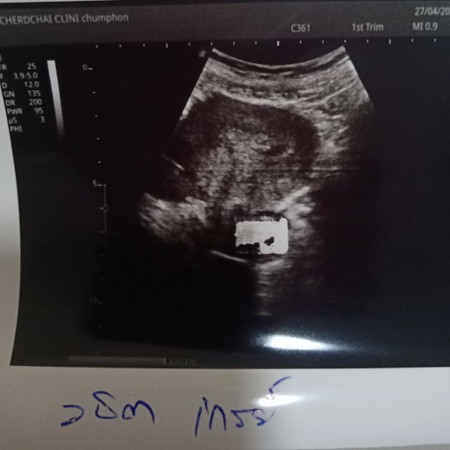

บ้านนี้ เจอถุงตั้งครรภ์เล็กๆเองค่ะ ตอน 4w4d ตามภาพค่ะ เจอถุงตั้งครรภ์กลมๆ ตอน 6w5d เจอน้องและเสียงหัวใจน้องตอน 13w1d